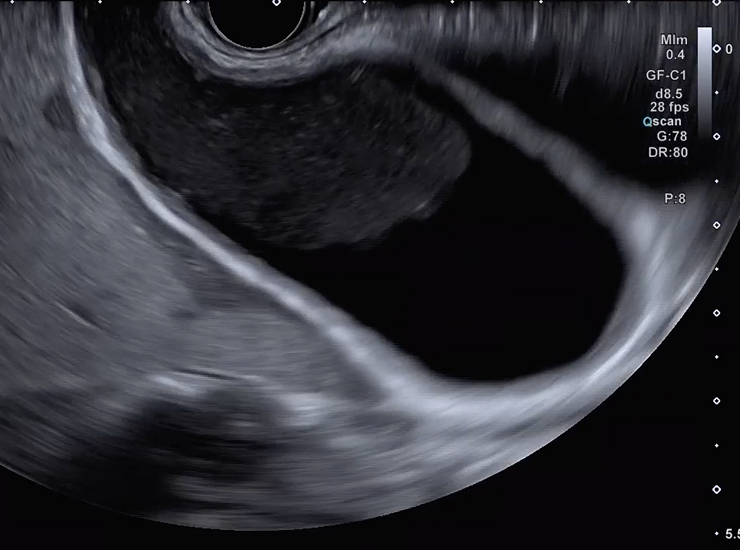

Contrast Harmonic Imaging (CHI)

CHI is the application of an ultrasound contrast agent to traditional ultrasonography to characterize focal liver lesions. Contrast agents are comprised of gas-filled microbubbles that are administered intravenously. The difference in echogenicity between the gas in the microbubbles and the soft tissue surrounding the body is immense, which improves the visualization and assessment of tissue vascularity.2